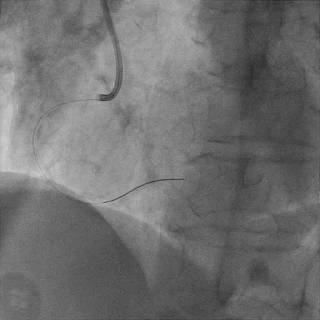

双侧造影,观察闭塞起始位置、长度、走行等

尝试通过RCA-圆锥支侧枝逆向开通LAD :

微导管辅助下,用SUOH03导丝尝试送入侧枝

经微导管TIP injection可见侧枝重度迂曲

侧枝重度迂曲,反复尝试未能通过